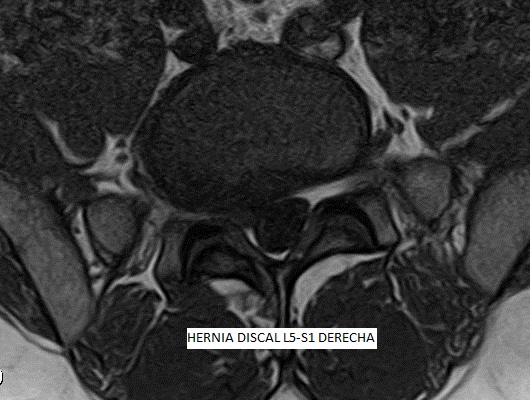

Las patologías del disco intervertebral se consideran de significativa contribución a la sensación dolorosa. Las hernias discales, protusiones discales y la artrosis, son las patologías degenerativas más comunes. La causa más frecuente del DOLOR LUMBAR es la degenerativa, asociada a cambios biomecánicos en la columna vertebral, resultando en un daño que puede alcanzar severa intensidad y provocar una gran limitación de nuestra calidad de vida.

La TERAPIA REGENERATIVA NEUROESPINAL, desarrollada por el equipo de Neurocirugía de la Clínica del Remei (COT- Neurocirugía Remei) y dirigida por la Dra. Ivón González Valcárcel, es una Intervención novedosa y mínimamente invasiva exenta de reacciones adversas, avalada por evidencia científica, que utiliza la biotecnología. Nos brinda beneficios inmediatos en el control del DOLOR LUMBAR, así como ofrece efectividad en revertir la cascada degenerativa, con la consecuente REPARACIÓN y REGENERACIÓN del disco intervertebral y otros tejidos afectados.